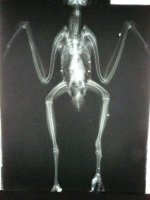

“Once” se recupera en el Hospital de Fauna de las graves lesiones sufridas por disparo . Superada la fase quirúrgica, su único recurso es la Fisioterapia y sus inmensas ganas de vivir.

- Once perdigones.

- Once impactos mortales.

- “Once” salvó su vida porque ninguno le acertó en un centro vital.

A Once le han quedado unas secuelas irreparables. Los perdigones alojados en su miembro inferior izquierdo han provocado una deformidad en varo de la extremidad y rotación interna. Los primeros días experimentó una reacción defensiva de su organismo a dichos perdigones conocida como granuloma a cuerpo extraño.

No era viable operar puesto que la metralla había fragmentado el hueso. La inflamación provocó a su vez un éstasis vascular y una paresia de la extremidad.

El miembro superior derecho también presentaba una fractura que no pintaba bien, pero con esa sí se atrevió el equipo de veterinarios.